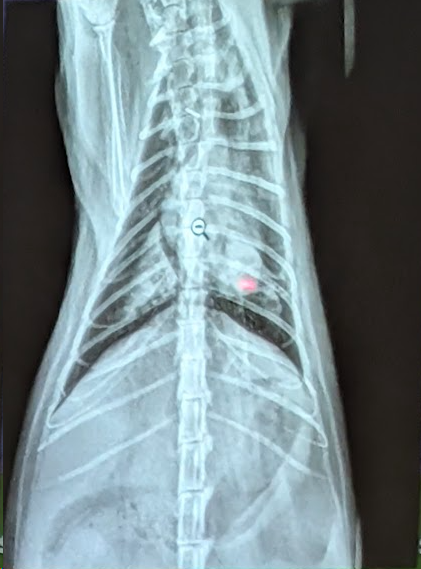

Preguna 1 - Multiple respuesta

- Se trata de un abdomen de gato

- Obstrucción intestinal

- Presenta una dilatación gastrica sin torsión (ya que el fundus y piloro gastrico están en su sitio).